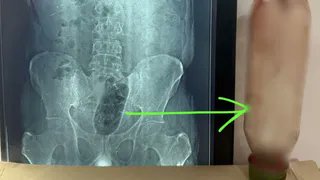

आगरा। उत्तर प्रदेश के आगरा ज़िले से बेहद चौंकाने वाला मामला सामने आया है। यहाँ एक शख्स ने अपनी अप्राकृतिक यौन इच्छा को पूरा करने के लिए 1 लीटर पानी की बोतल अपने मलद्वार के जरिए शरीर के अंदर घुसा ली, जो फंस गई। करीब 36 घंटे तक बोतल शरीर के अंदर रहने के कारण शख्स की हालत गंभीर हो गई, जिसके बाद डॉक्टरों ने सर्जरी कर उसे बाहर निकाला। क्या था मामला? मिली जानकारी के अनुसार, पीड़ित ने खुद ही बोतल को मलद्वार के रास्ते अंदर प्रवेश कराया था। हालांकि, बोतल के फंस जाने के बाद उसे गंभीर दर्द और सांस लेने में तकलीफ होने लगी। जब दर्द असहनीय हो गया, तो उसे तत्काल अस्पताल ले जाया गया। डॉक्टरों ने एक्स-रे और अन्य जांच की, जिसमें मलाशय के भीतर बोतल स्पष्ट दिखाई दी।मामले की गंभीरता को देखते हुए डॉक्टरों की एक टीम ने तुरंत सर्जरी का निर्णय लिया। सर्जरी के माध्यम से लगभग 36 घंटे बाद बोतल को शरीर से सफलतापूर्वक बाहर निकाला गया। डॉक्टरों के अनुसार, यह कोई सामान्य दुर्घटना नहीं, बल्कि एक साइको-सेक्सुअल डिसऑर्डर’ का मामला है। आगरा में एक शख्स ने 1 लीटर पानी की बोतल मलद्वार से अपने अंदर घुसा ली। 36 घंटे तक वो फंसी रही। हॉस्पिटल में सर्जरी करके बोतल निकाली गई।डॉक्टरों के अनुसार, यह साइको सेक्सुअल डिसऑर्डर है। जिसमें ऐसे लोग गुदा और मलाशय द्वार से जुड़ी यौन क्रिया करते हैं, इससे इन्हें आनंद मिलता है। pic.twitter.com/DEbwlvlU4m— Sachin Gupta (@SachinGuptaUP) March 15, 2026 मलाशय से जुड़ी यौन क्रियाएं करने से मिलता है आनंद चिकित्सकों ने बताया कि साइको-सेक्सुअल डिसऑर्डर से ग्रस्त लोग गुदा और मलाशय से जुड़ी यौन क्रियाएं करते हैं, जिससे उन्हें मानसिक और शारीरिक आनंद प्राप्त होता है। फ़िलहाल यह पूरी घटना सोशल मीडिया पर तेज़ी से वायरल हो रहा है। Post Views: 63 Please Share With Your Friends Also Post navigation महिला ने चप्पल दिखाकर दी गाली, बीवी तक पहुंची बात तो युवक ने कर दिया ऐसा कांड वायरल वीडियो देख दंग रह जाएंगे आप वायरल मोनालिसा निकली नाबालिग! ST आयोग की रिपोर्ट में हुआ खुलासा, इतने साल की है वायरल गर्ल, पति फरमान की बढ़ी मुश्किलेंं